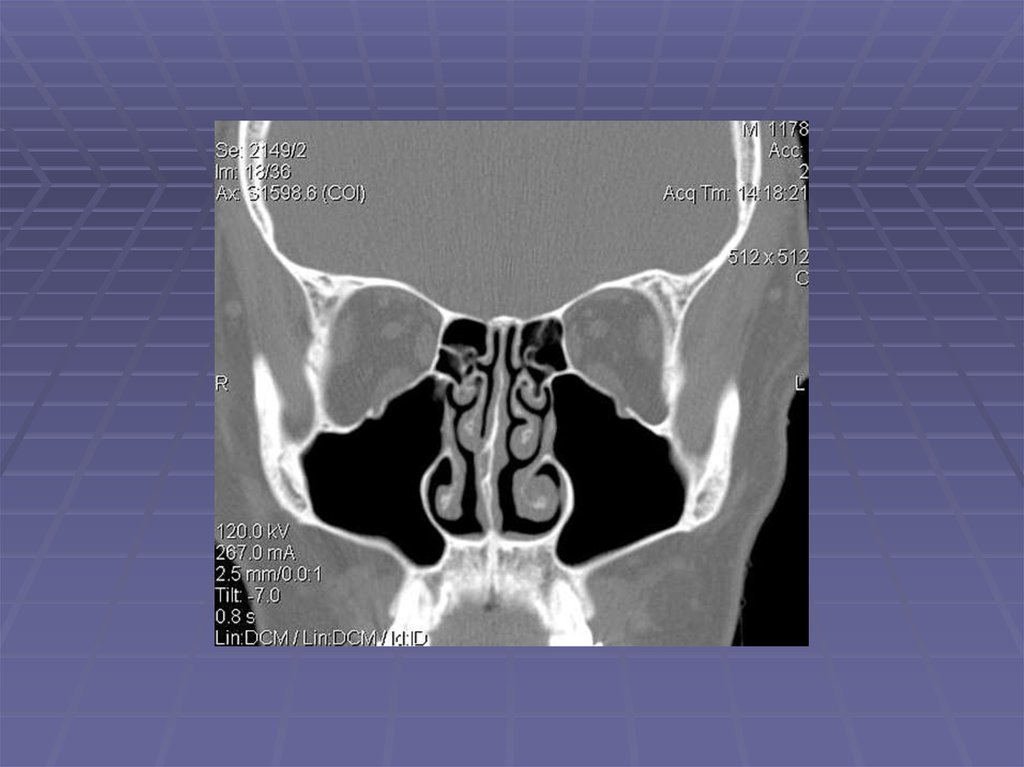

Череп